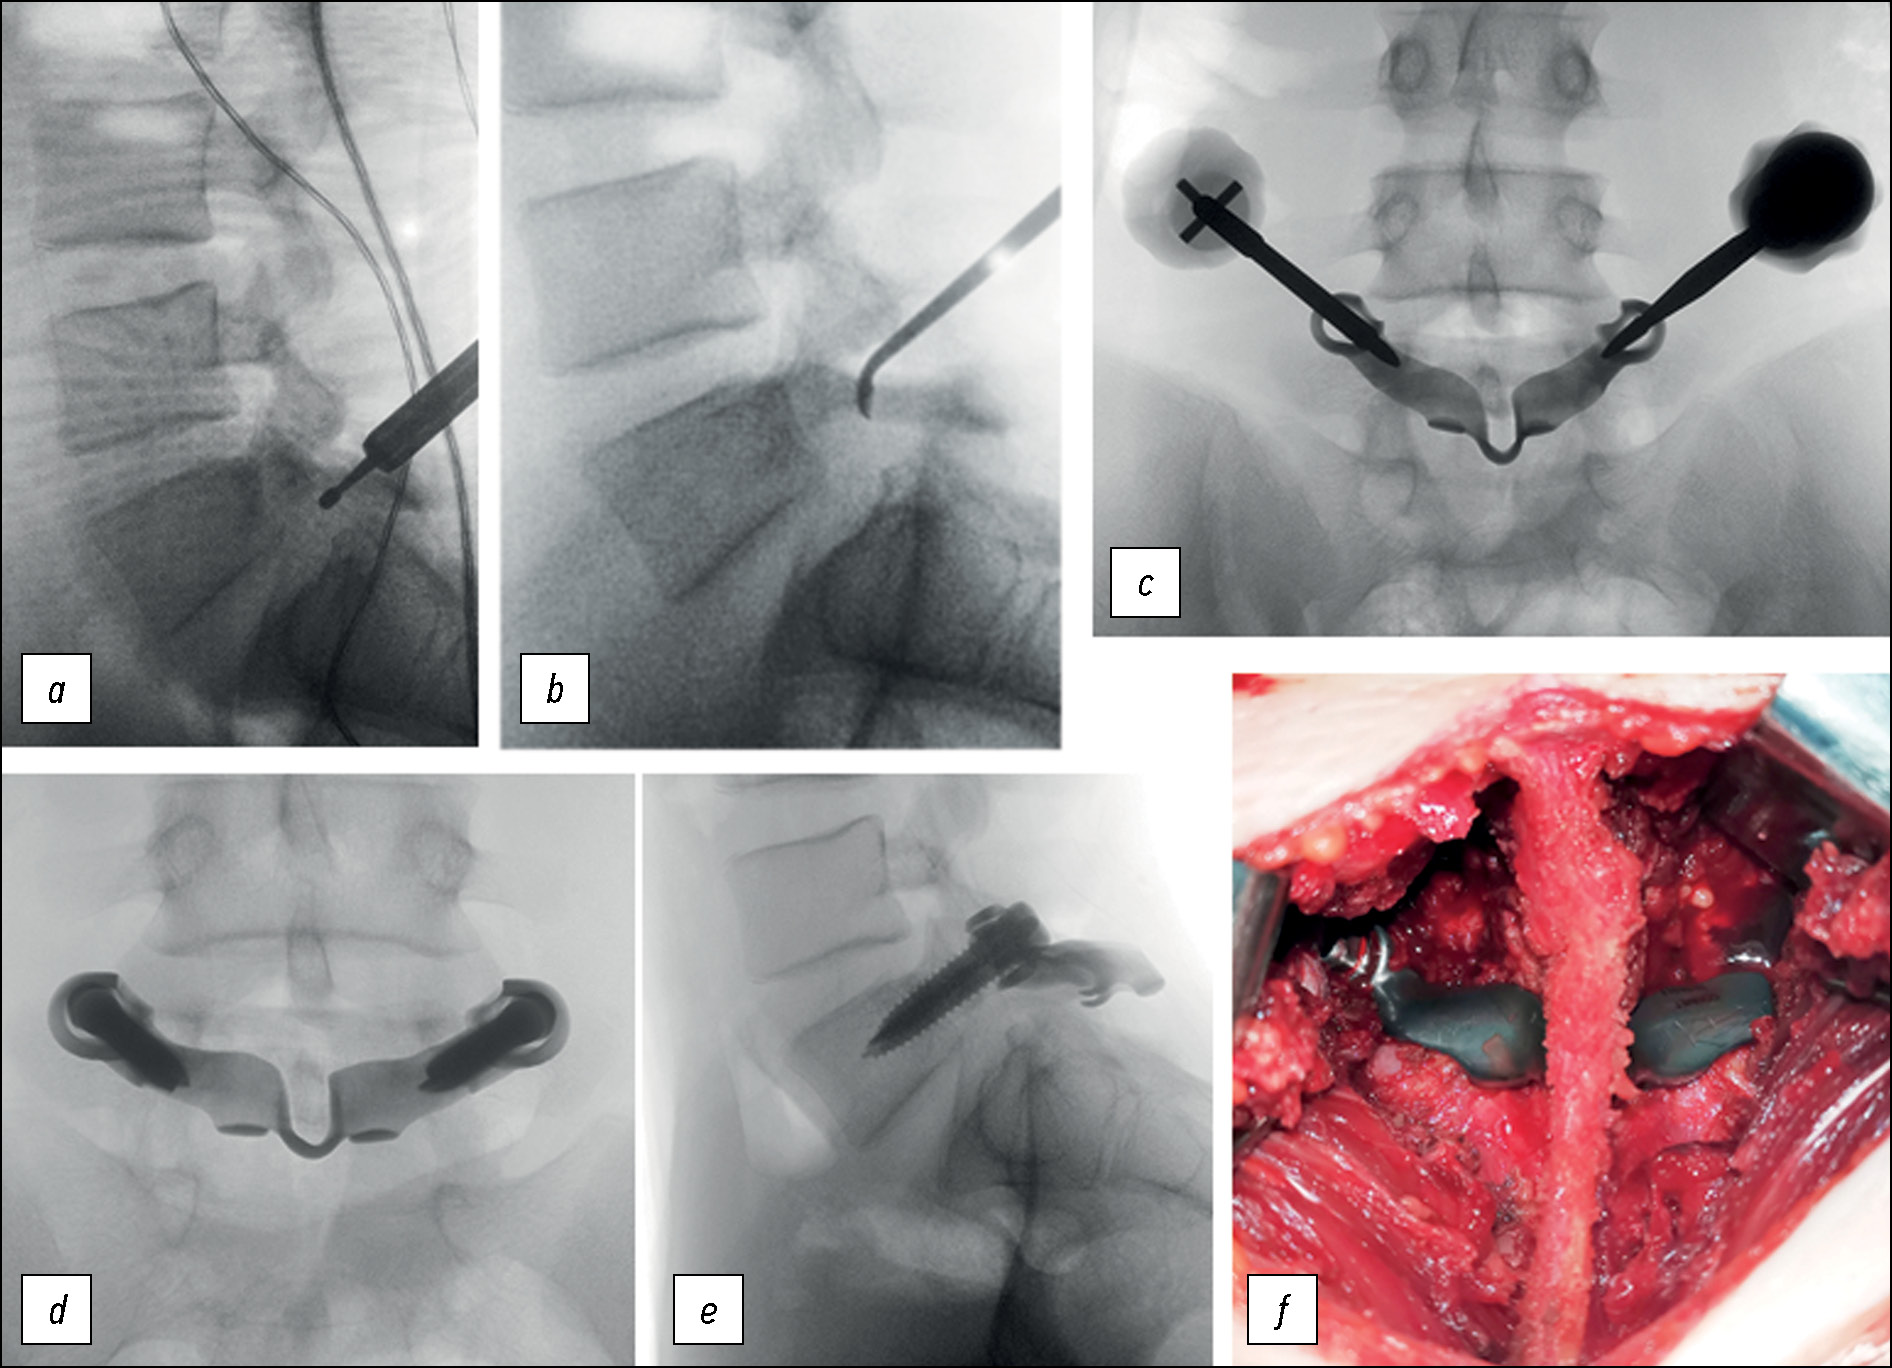

Рис. 4. Флюороскопический контроль во время операции и внешний вид установленной конструкции: а, b — обработка зоны спондилолиза, c — установка транспедикулярных винтов, d, e — ЭОП-контроль положения конструкции, f — внешний вид установленной конструкции, сохранённая надостистая связка.

Fig. 4. Fluoroscopic control during surgery and the appearance of the installed implant: a, b — preparing of the spondylolysis zone, c — pedicular screws isertion, d, e — fluoroscopic control, f — appearance of the installed custom-made imlant with preserved supraspinous ligament.

Ход операции: в положении пациентки на животе под интубационным наркозом выполнен разрез кожи и подкожно-жировой клетчатки по линии остистых отростков от L5 до S1. Произведено скелетирование дуги L5 с сохранением надостистой связки. Выполнен гемостаз. С помощью высокооборотистой дрели и костных ложек произведён кюретаж зоны спондилолиза с обеих сторон (рис. 4а, b). С помощью ламинотомов удалена межостистая связка L5-S1. Изогнутым распатором выполнено скелетирование дужки в месте осуществления субламинарной фиксации. Установлена индивидуальная пластина на скелетированную дужку L5 позвонка, причём пластина проведена между остистыми отростками соответственно L5 и S1 позвонков. Чрескожно под контролем с применением электронно-оптического преобразователя (ЭОП) и визуального контроля через отверстия в конструкции в корни дуг L5 позвонка с обеих сторон проводятся транспедикулярные винты (рис. 4с).

При вкручивании винтов за счёт конструкции их головок пластина плотно прижата к дужке позвонка и фиксирована. Проведён рентген-контроль при помощи ЭОП в двух проекциях, подтверждено правильное положение имплантатов (рис. 4d, e, f). Рана промыта раствором антисептика, послойно ушита, выполнен внутрикожный косметический шов. Кровопотеря составила 50 мл. Послеоперационное течение без особенностей. Пациентка вертикализирована в первые сутки после операции. Отмечала умеренные боли в области послеоперационной раны, которые купированы приёмом нестероидных противовоспалительных препаратов в течение 3 дней. Выполнено контрольное КТ-исследование, подтверждены правильное положение имплантатов и фиксация зоны спондилолиза. На пятые сутки после операции пациентка выписана под амбулаторное наблюдение. Рана зажила первичным натяжением.